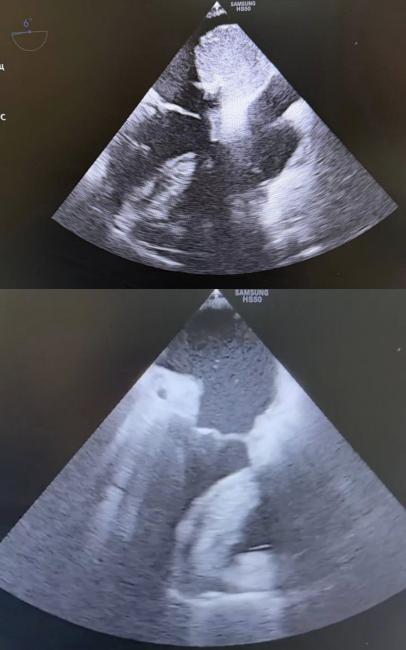

У Вінницькій обласній клінічній лікарні ім. М. І. Пирогова лікарі провели складну кардіохірургічну операцію та врятували жінку з небезпечною внутрішньосерцевою пухлиною. Міксома у лівому передсерді рухалася синхронно з кожним ударом серця, створюючи постійну загрозу життю.

За словами медиків, кожне скорочення серця відбувалося в умовах подвійного ризику: раптового перекриття клапанного отвору та системної емболії з потенційно фатальними наслідками.

Операцію провели в умовах штучного кровообігу. Хірурги виконали атріотомію та радикально видалили міксому. Після втручання внутрішньосерцеву анатомію вдалося повністю відновити, а показники гемодинаміки — стабілізувати.